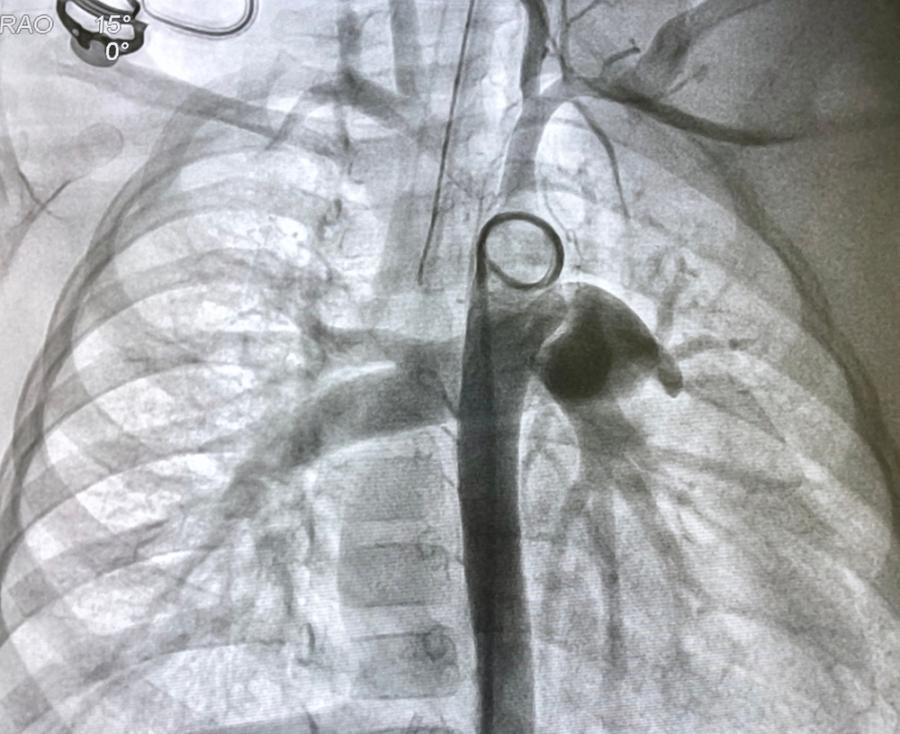

През 1929-та Форсман е бил лекар, практикуващ в болница в Еберсвалде – на север от Берлин. Той е вярвал, че може да постави катетър на сърцето, като вкара тръбичка във вена, намираща се в областта на лакътя, и я избута чак до органа. За времето си подобна идея е изглеждала безумна и немислима. По-старши лекарите от него са я отхвърляли, тъй като са вярвали, че това ще доведе до смъртта на пациента.

Впоследствие продължава да се преструва, че я подготвя за катетеризацията. Всъщност просто очаквал упойката да започне да действа. Щом това се случило, разрязал ръката си, вкарал катетъра 30 см в собствената си вена и казал на Герда да викне сестрата, отговаряща за рентгена, тъй като тя ще му бъде необходима за следващата част от процедурата.

Чак в този момент Герда осъзнава, че катетърът не е в нейната ръка. Първоначално започва да протестира, но в края на краищата го отвежда в рентгеновото отделение на по-долния етаж. Докато се опитвал да направи рентген върху самия себе си, за да види докъде е стигнала тръбичката, Питър Ромелс – негов близък приятел – се намесва и се опитва да извади катетъра.